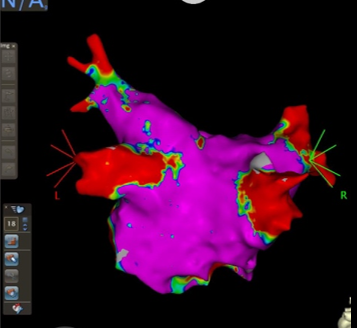

心房細動、心房粗動、発作性上室頻拍をはじめとした頻脈性不整脈に対して、洞調律維持を目指して、カテーテルアブレーションを中心とした治療を行っています。3次元マッピングシステムとして、CARTO®3およびEnSite™を用いて、放射線被ばくの低減や難治性不整脈に対する治療成功率の上昇を図っています。

CARTO®3での左房のVoltage Map

(左心房を後方から見た像)

症例患者様:70代 男性

症例治療内容:持続性心房細動に対して両側肺静脈隔離術

症例治療期間・回数:入院期間:3泊4日、手術時間:1時間30分、入退室2時間、初回症例